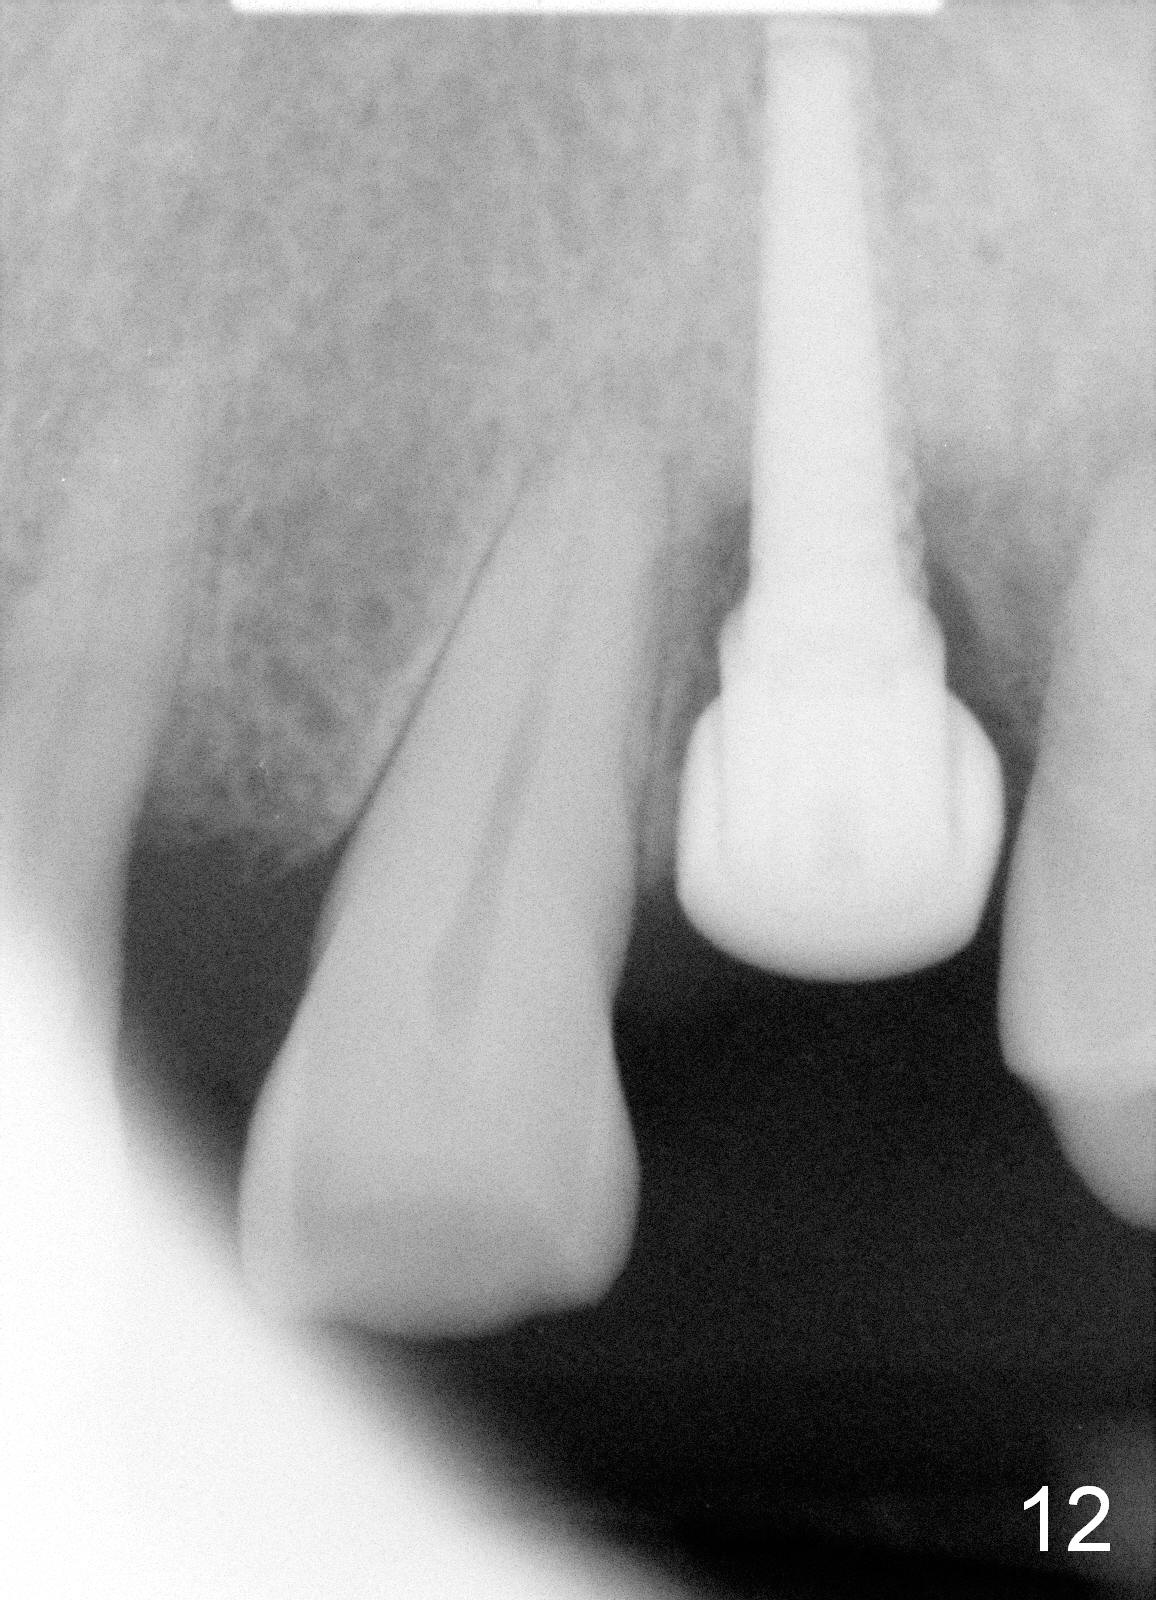

Crestal bone grows 2 months (Fig.11), 3 months (Fig.12), 1 year (Fig.13) and 2 years 3 months (Fig.14) postop. When the periodontally-affected tooth is removed and bone graft is placed around the most coronal thread of the implant, bone will regrow as time passes by.